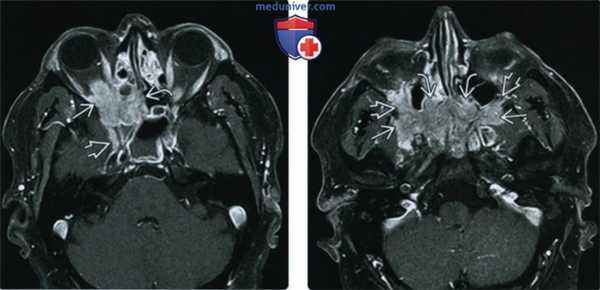

(Слева) При MPT Т1ВИ FS с КУ в аксиальной проекции определяется обширный контрастный идиопатический воспалительный псевдотумор, инфильтрирующий верхушку глазницы, решетчатый лабиринт и круглое отверстие.

(Справа) При МРТ T1ВИ с КУ в аксиальной проекции (срез проходит ниже) у этого же пациента определяется двусторонний псевдотумор крылонебной ямки, непосредственно соединенный с идиопатическим воспалительным псевдотумором полости носа. Также поражены обе нижние глазничные щели. Обширные идиопатические воспалительные псевдотуморы глаз-ниц/внеглазничной локализации зачастую трудно поддаются лечению стероидами.

(Слева) МРТ, постконтрастное Т1-ВИ, режим подавления сигнала от жира, аксиальный срез: определяется зона контрастирования идиопатического внеглазничного воспаления (ИВВ), вовлекающая правый пещеристый синус с легким сужением внутрипещеристого отдела соответствующей внутренней сонной артерии.

(Справа) МРТ, Т2-ВИ, аксиальный срез: у этого же пациента наблюдается зона идиопатического воспаления глазницы (ИВГл), связанная с зоной ИВВ в области пещеристого синуса через верхнюю глазничную щель. Обе зоны идиопатического воспаления характеризуются гипоинтенсивным сигналом вследствие фиброза, который часто наблюдается при данном состоянии. (Слева) МРТ, постконтрастное Т1 -ВИ, режим подавления сигнала от жира, аксиальный срез через глазницы: визуализируется утолщение и контрастное усиление прямых мышц глаза, связанных воспалительным процессом через ВГЩ с пещеристым синусом и карманом Меккеля. В связи с подозрением на аденоидно-кистозный рак была проведена биопсия и выявлено идиопатическое воспаление как с внутриглазничным, так и с внутричерепным компонентами.

(Справа) МРТ, постконтрастное Т1-ВИ, режим подавления сигнала от жира, аксиальный срез: у этого же пациента определяется инвазия поражения через нижнюю глазничную щель в нижерасположенные структуры: в крылонебную ямку и структуры носа.